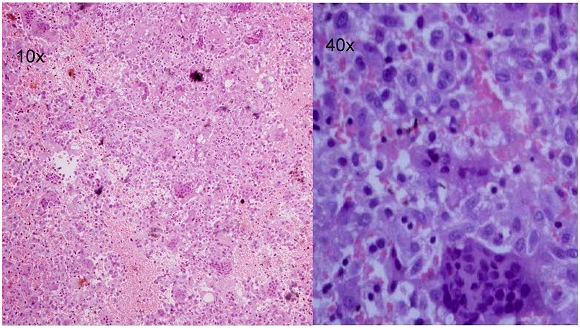

Figure 2 H&E Stained section show large osteoclast like giant cells and uniform ovoid mononuclear cells (Giant Cell Tumor).